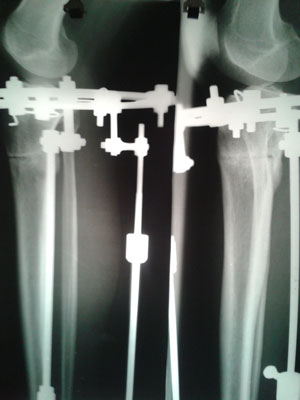

Рентген перед снятием аппаратов.

Вложения

20150107_115900.jpg

20150107_120009.jpg

Дата операции 25.08.2014г.

Дата снятия аппаратов 07.01.2015г.

Срок лечения 132 дня.